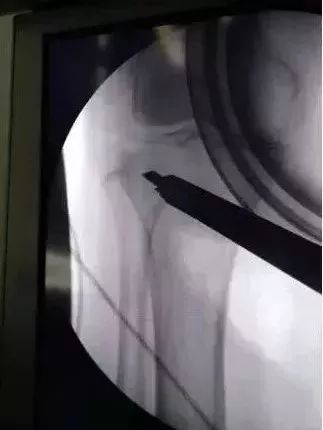

术中手术透视克氏针定位